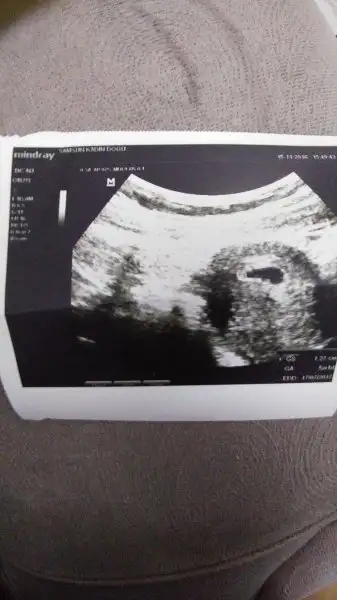

Birde böyle sorunlar mi varmış ilk defa duyuyorum neler öğreniyor insanKızlar internette okumuştum kesenin yusvuvsrlak olması gerekiyomuş benim ilk baktığımızda yusyuvarlaktı daha sonra gittiğimde değişikti bi bakar mısınız ? Bozulmuş kese mi benim ki

Benim kesem duzensizdi ama senin ki normal görünüyor zaten ole bisey olsa doktorun solerdi kafaya takma daha koskoca , 8 ayın var baciMKızlar internette okumuştum kesenin yusvuvsrlak olması gerekiyomuş benim ilk baktığımızda yusyuvarlaktı daha sonra gittiğimde değişikti bi bakar mısınız ? Bozulmuş kese mi benim ki